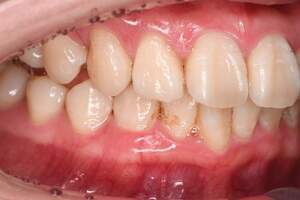

スケーリング

| 年齢 | 45歳・男性 |

|---|---|

| 主訴 | 歯石をとりたい |

| 治療内容 | 全顎歯石除去 |

| 治療期間 | 60分 |

| 費用 | 約2,000円(保険適用) (2022年7月現在) |

| 治療方針 | 約4年ぶりの歯科医院で歯のクリーニングを行いたいと来院されました。 歯石除去と歯の表面に付着したプラークを取り除きました。また、ご自身でしっかり歯磨きができるように、歯ブラシのレッスンも行いました。 |

| 担当者所見 | 歯石がなくなった変化に驚き、すっきりしたと喜んでくださいました。歯周病の進行がみられるので次回以降歯周病治療を行っていきます。 |